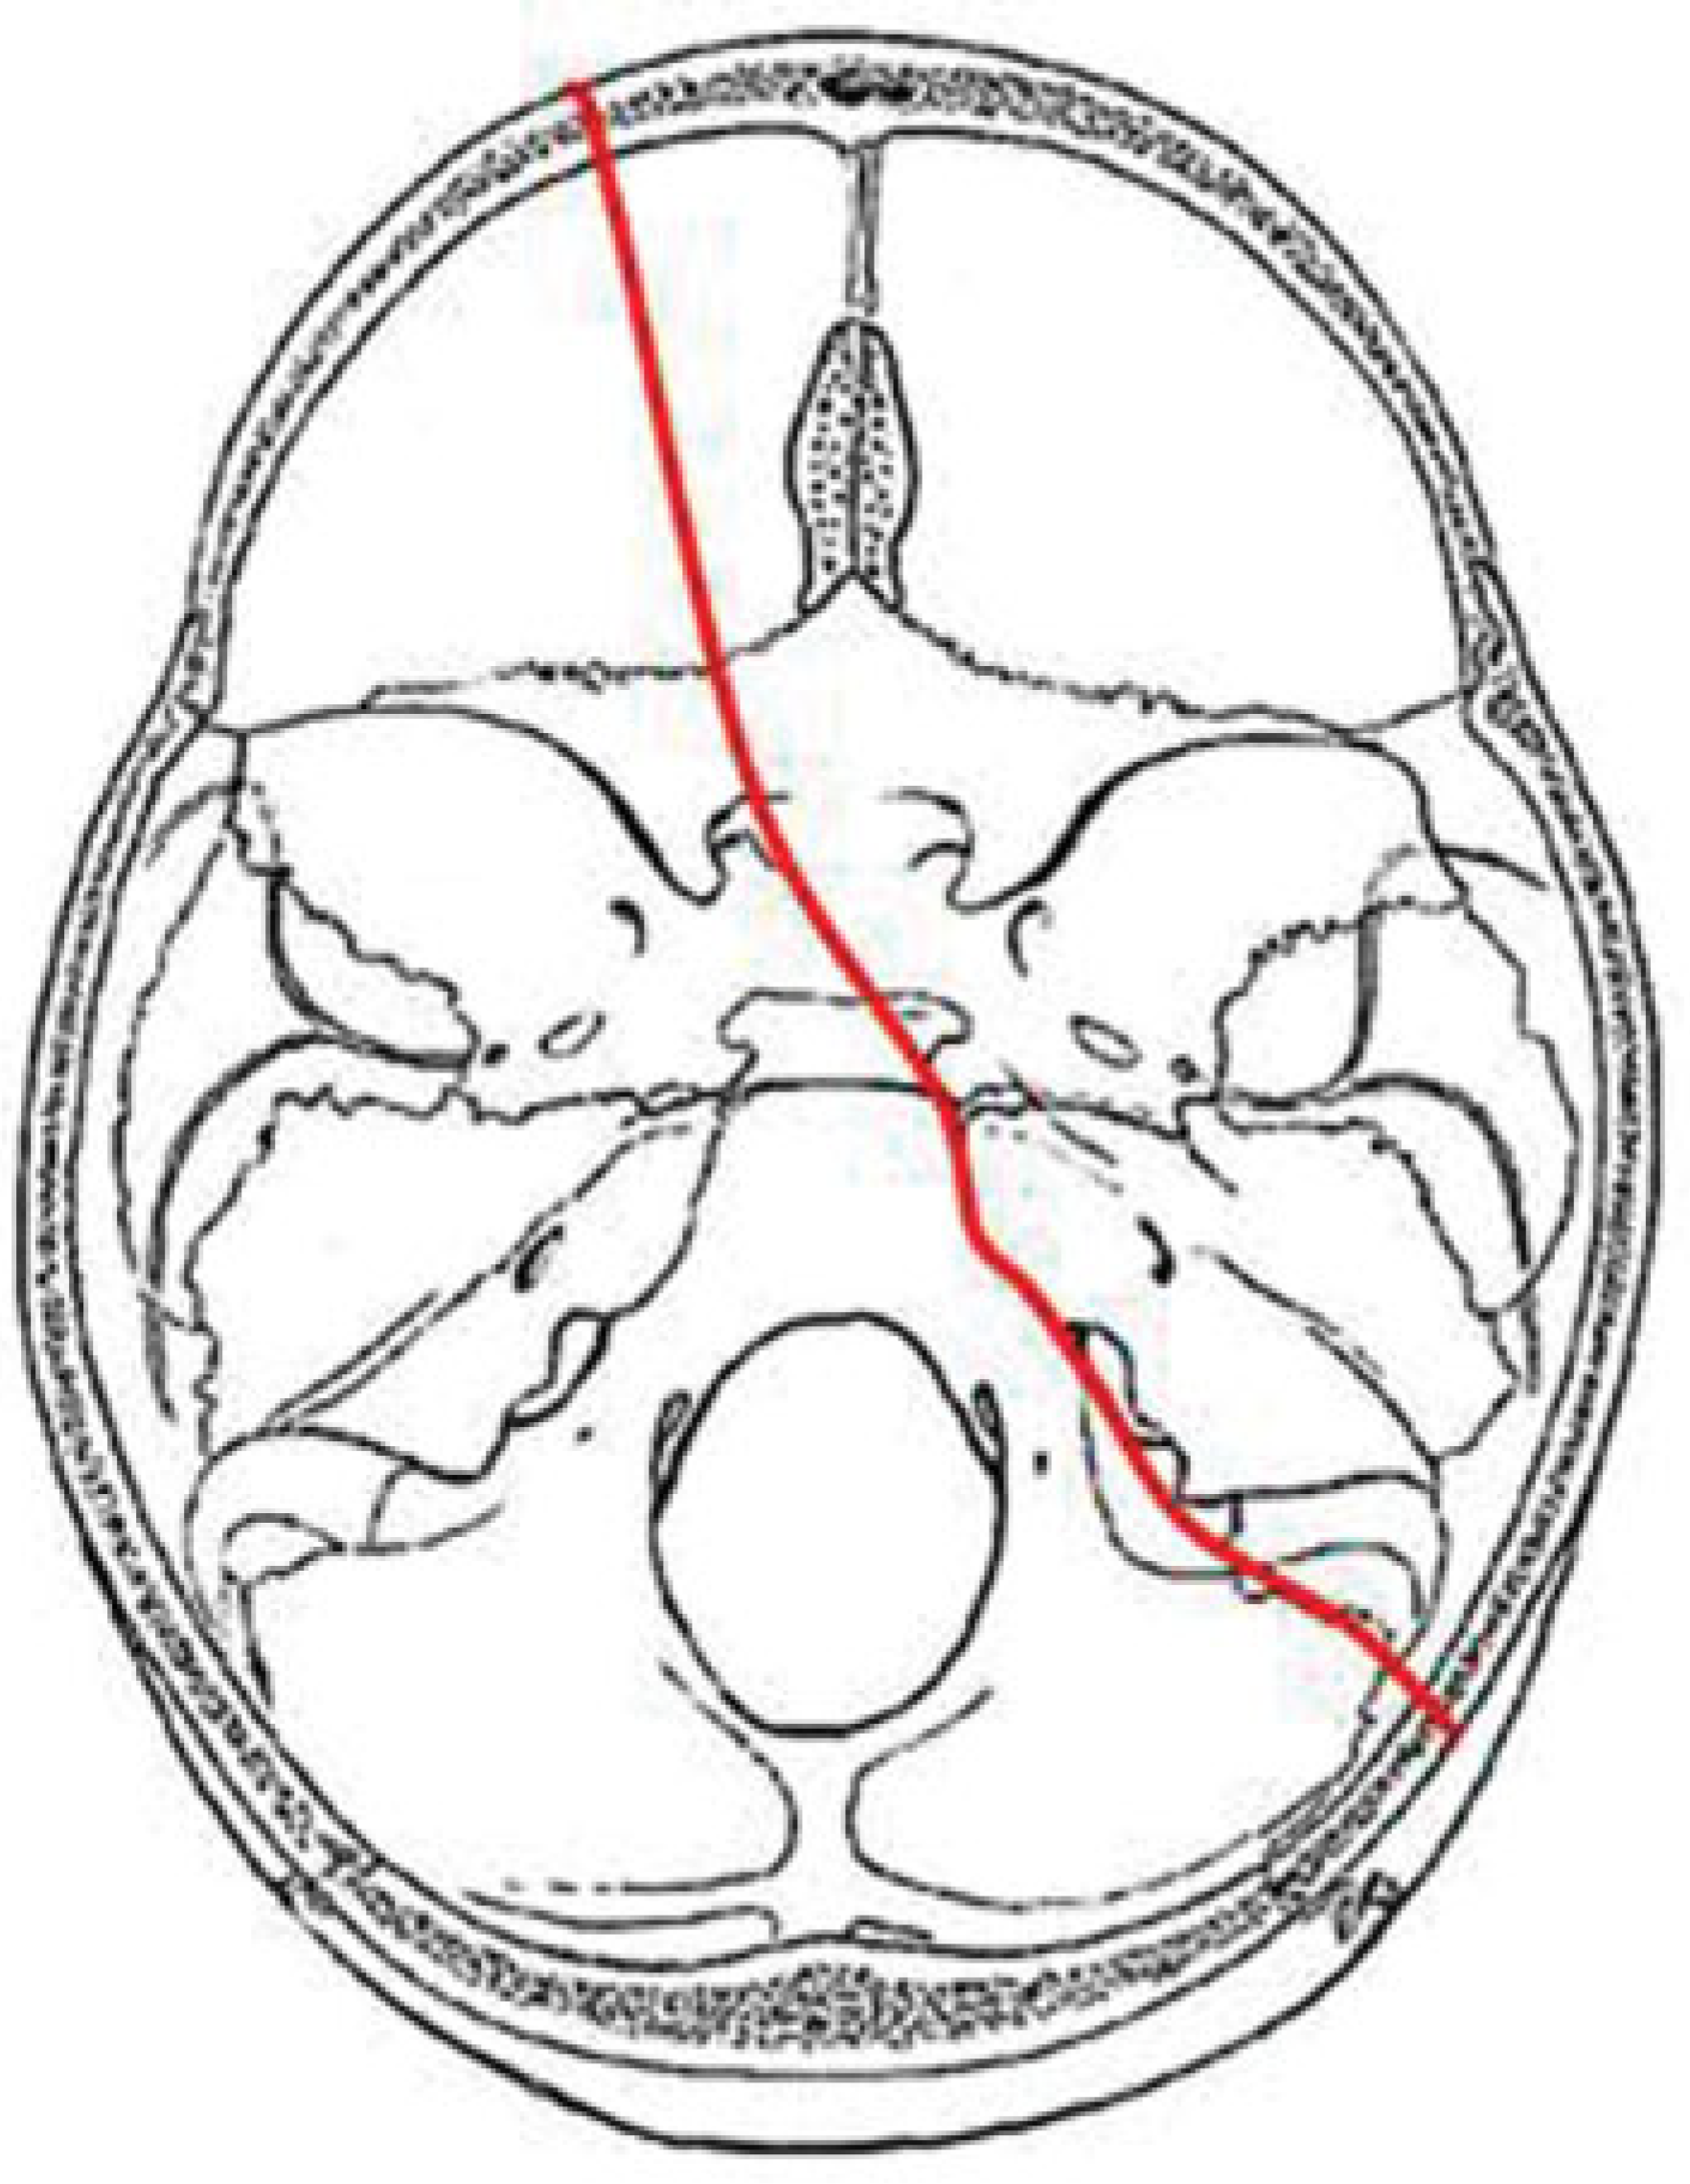

In our study we identified four major fracture patterns of transsphenoidal basilar skull fractures, which were: anterior transverse (AT), lateral frontal diagonal (LFD), posterior trans-verse (PT), and mastoid diagonal (MD), which matches Clark’s descriptions of the transsphenoidal basilar skull fractures.17

LFD Pattern

The LFD fracture pattern occurs as the result of impact to the lateral frontal region or the anterior malar eminence. Force appears to be transmitted along the lateral orbital and/or lateral maxillary sinus wall to the sphenotemporal buttress. From the sphenotemporal buttress, the force is transmitted along the ipsilateral sphenoid sinus wall to the posterior wall of the sphenoid sinus. The fracture may cross the sphenoid body in a transverse plane or in a diagonally plane. The fracture continues through or immediately anterior to the contralateral carotid canal into the sphenopetrosal syn-chondrosis. The fracture may then continue through the tympanic portion of the temporal bone (Figure 6).

Figure 6. Composite drawing of the lateral frontal diagonal pattern (left impact).